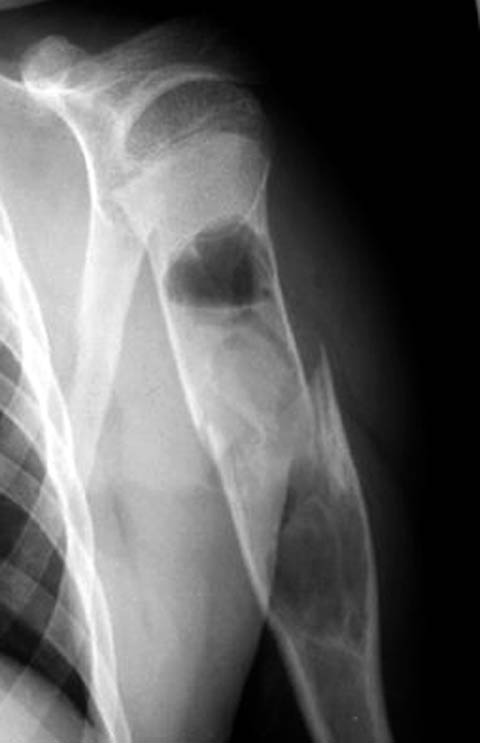

И второй снимок

Противоположный сустав.JPG

Снимок выглядит нормальным. Обратите внимание, в каком положении он сделан.

Если во внутренней ротации - то это совершенно нормальная картина.

Сделайте снимок здорового плечевого сустава в прямой проекции но с максимальной наружной ротацией или внутренней ротацией плеча и увидите в головке такую же "шарополость" с костной структурой ничем не похожую на аневризмальную кисту.

Я согласен с уважаемыми А.Семенистым и Л.Лапидус,на мой взгляд проблема в рентгенукладке,у нас ретгенлаборанты тоже частенько грешат,особено по ночам -выдают такие "аневризмальные" кисты.

Подозрение о "шаровидной полости" в головке - это из-за укладки, и на представленном снимке подтверждение правильности рекомендации коллег.